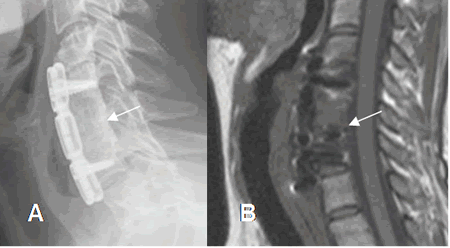

El estudio inicial con Rx simple es de mucha utilidad, por el amplio campo de visión que da. Las protecciones dinámicas permiten valorar la integridad de la fusión y el grado de movilidad. (28). (Fig 131 y 132).

Fig 131. Fusión postQx.

A: Rx lateral y B: RM sagital en T1. Instrumentación anterior con placas y tornillos, que produce fusión entre los cuerpos vertebrales.